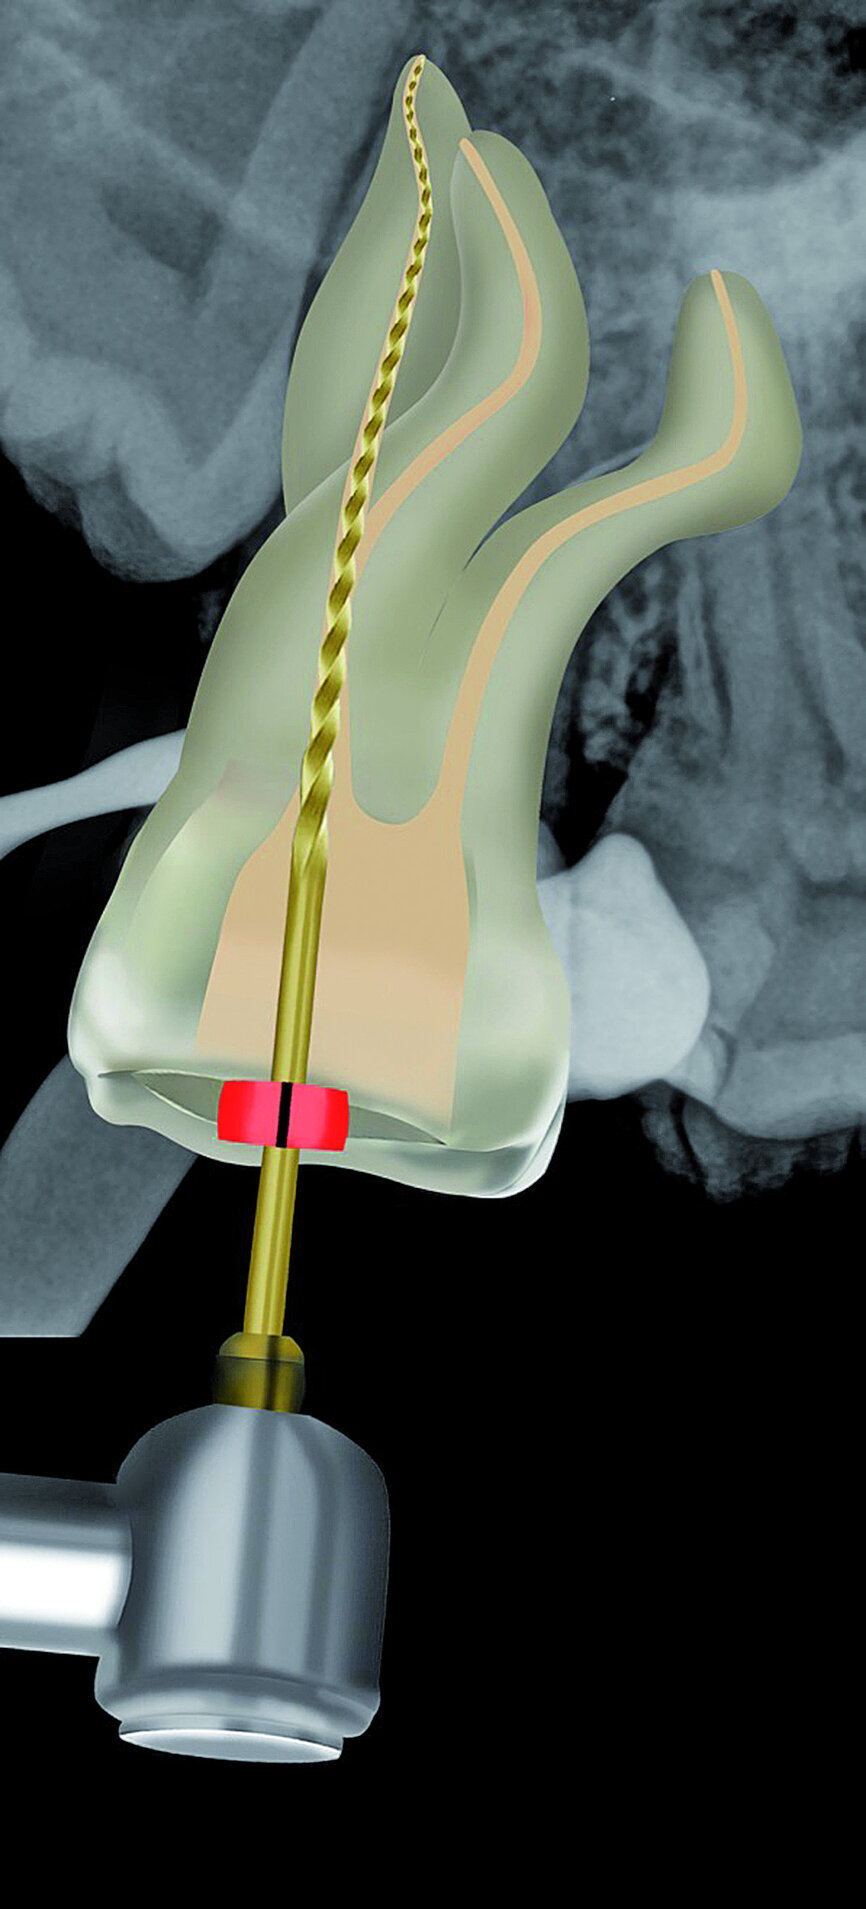

Fig. 23: A ProGlider was used in a rotary motion to expand the glide path in the palatal root canal.

The pulp chamber was filled with Glyde (Dentsply Sirona) before the canals were carefully negotiated to full working using pre-curved size 08 K-Files (Fig. 19). Working length measurements obtained from an electronic apex locator reading corresponded with the lengths obtained from the 3D Endo Software. These measurements were also confirmed radiographically (Fig. 20). A reproducible glide path was prepared in each root canal system with the size 08 K-File in an M4 Reciprocating handpiece (Sybron Endo; Fig. 21), followed by making a size 10 K-File ‘super loose’ (Fig. 22). A ProGlider (Dentsply Sirona) was used in a rotary motion to expand the glide path in the palatal root canal (Fig. 23). Considering the sharp and severe curvatures in the two buccal canals, it was decided to convert the ProGlider instrument into a manual file to expand the glide path in these tortuous canals with more safety (Fig. 24). The manually adapted ProGlider was used in a balanced force motion up to working length. In addition, to create more safety during the canal preparation of the two challenging buccal root canals, it was also decided to use the reciprocating WaveOne Gold Glider (Dentsply Sirona; Fig. 25), after the ProGlider instrument to further expand the glide paths. The WaveOne Gold Glider was used in 4–8 backstroke brushing motions from working length, in the two buccal root canal systems.